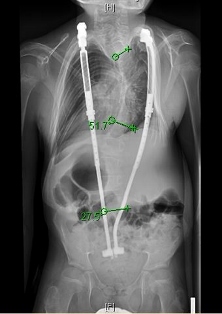

[An X-Ray showing the severity of Daniel Stephen's scoliosis and the placement of the titanium rods]

“He basically saved my life,” says 14 year old Daniel Stephens.  He’s talking about the man he calls his hero- Pediatric Orthopedic Surgeon Dr. Jonathan Phillips. Daniel has early onset scoliosis- that’s a progressive curvature of the spine that, if left untreated, would crush his lungs and kill him. The standard treatment is a set of surgically implanted titanium rods that slowly straighten his spine out. Dr. Phillips and Daniel’s parents, Dawn and Bill Stephens, pick up the story from here, beginning with Dr. Phillips.